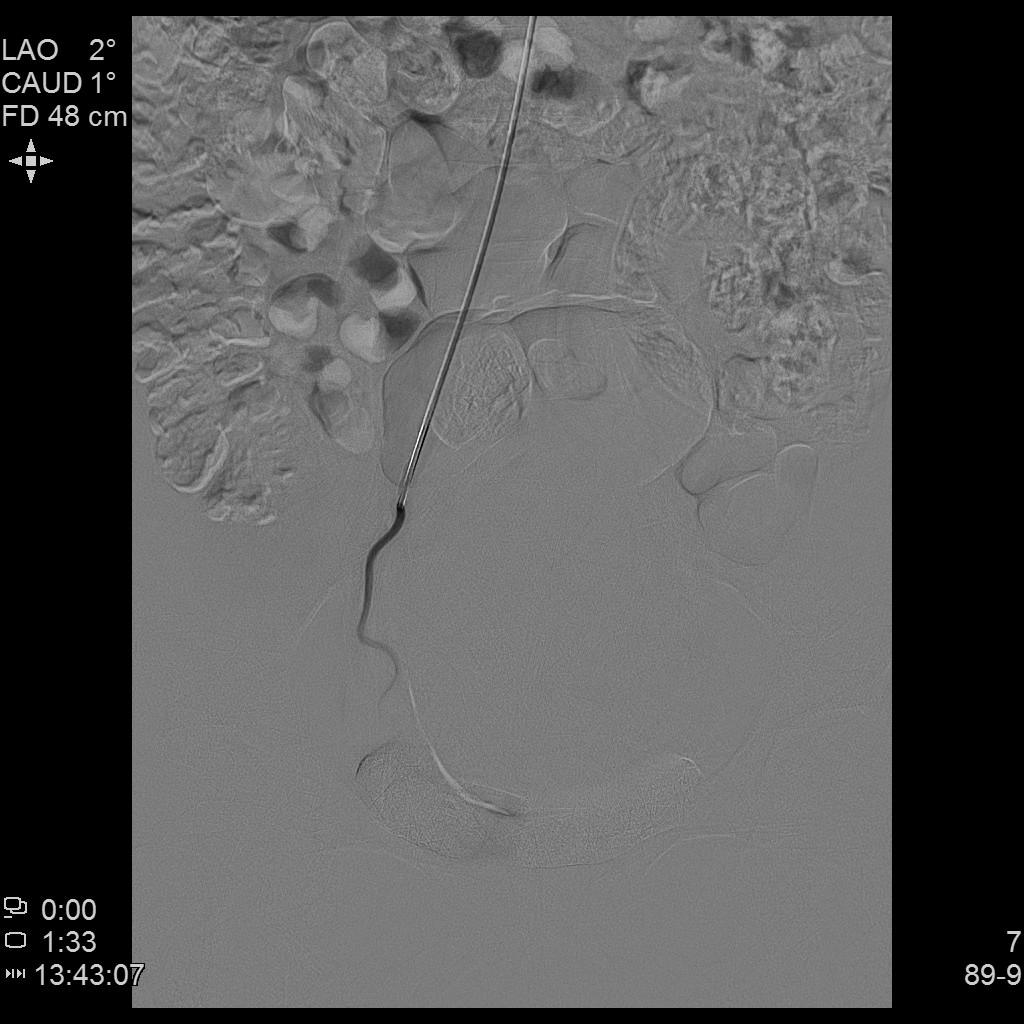

例4

中年女性,痛经10余年,近3个月明显加重。痛经达重度疼痛,严重影响生活质量。磁共振检查显示子宫前壁囊性病灶。临床诊断为囊性子宫腺肌症。

- 经左侧桡动脉穿刺置管,行腹主动脉造影显示双侧子宫动脉增粗、迂曲。

- 超选择插管右侧子宫动脉病灶供血动脉造影+栓塞治疗。

- 超选择插管左侧子宫动脉病灶供血动脉造影+栓塞治疗。

- 术后桡动脉压迫止血6小时,患者术后无需长时间卧床、下肢制动,舒适度明显提高,促进术后快速康复。